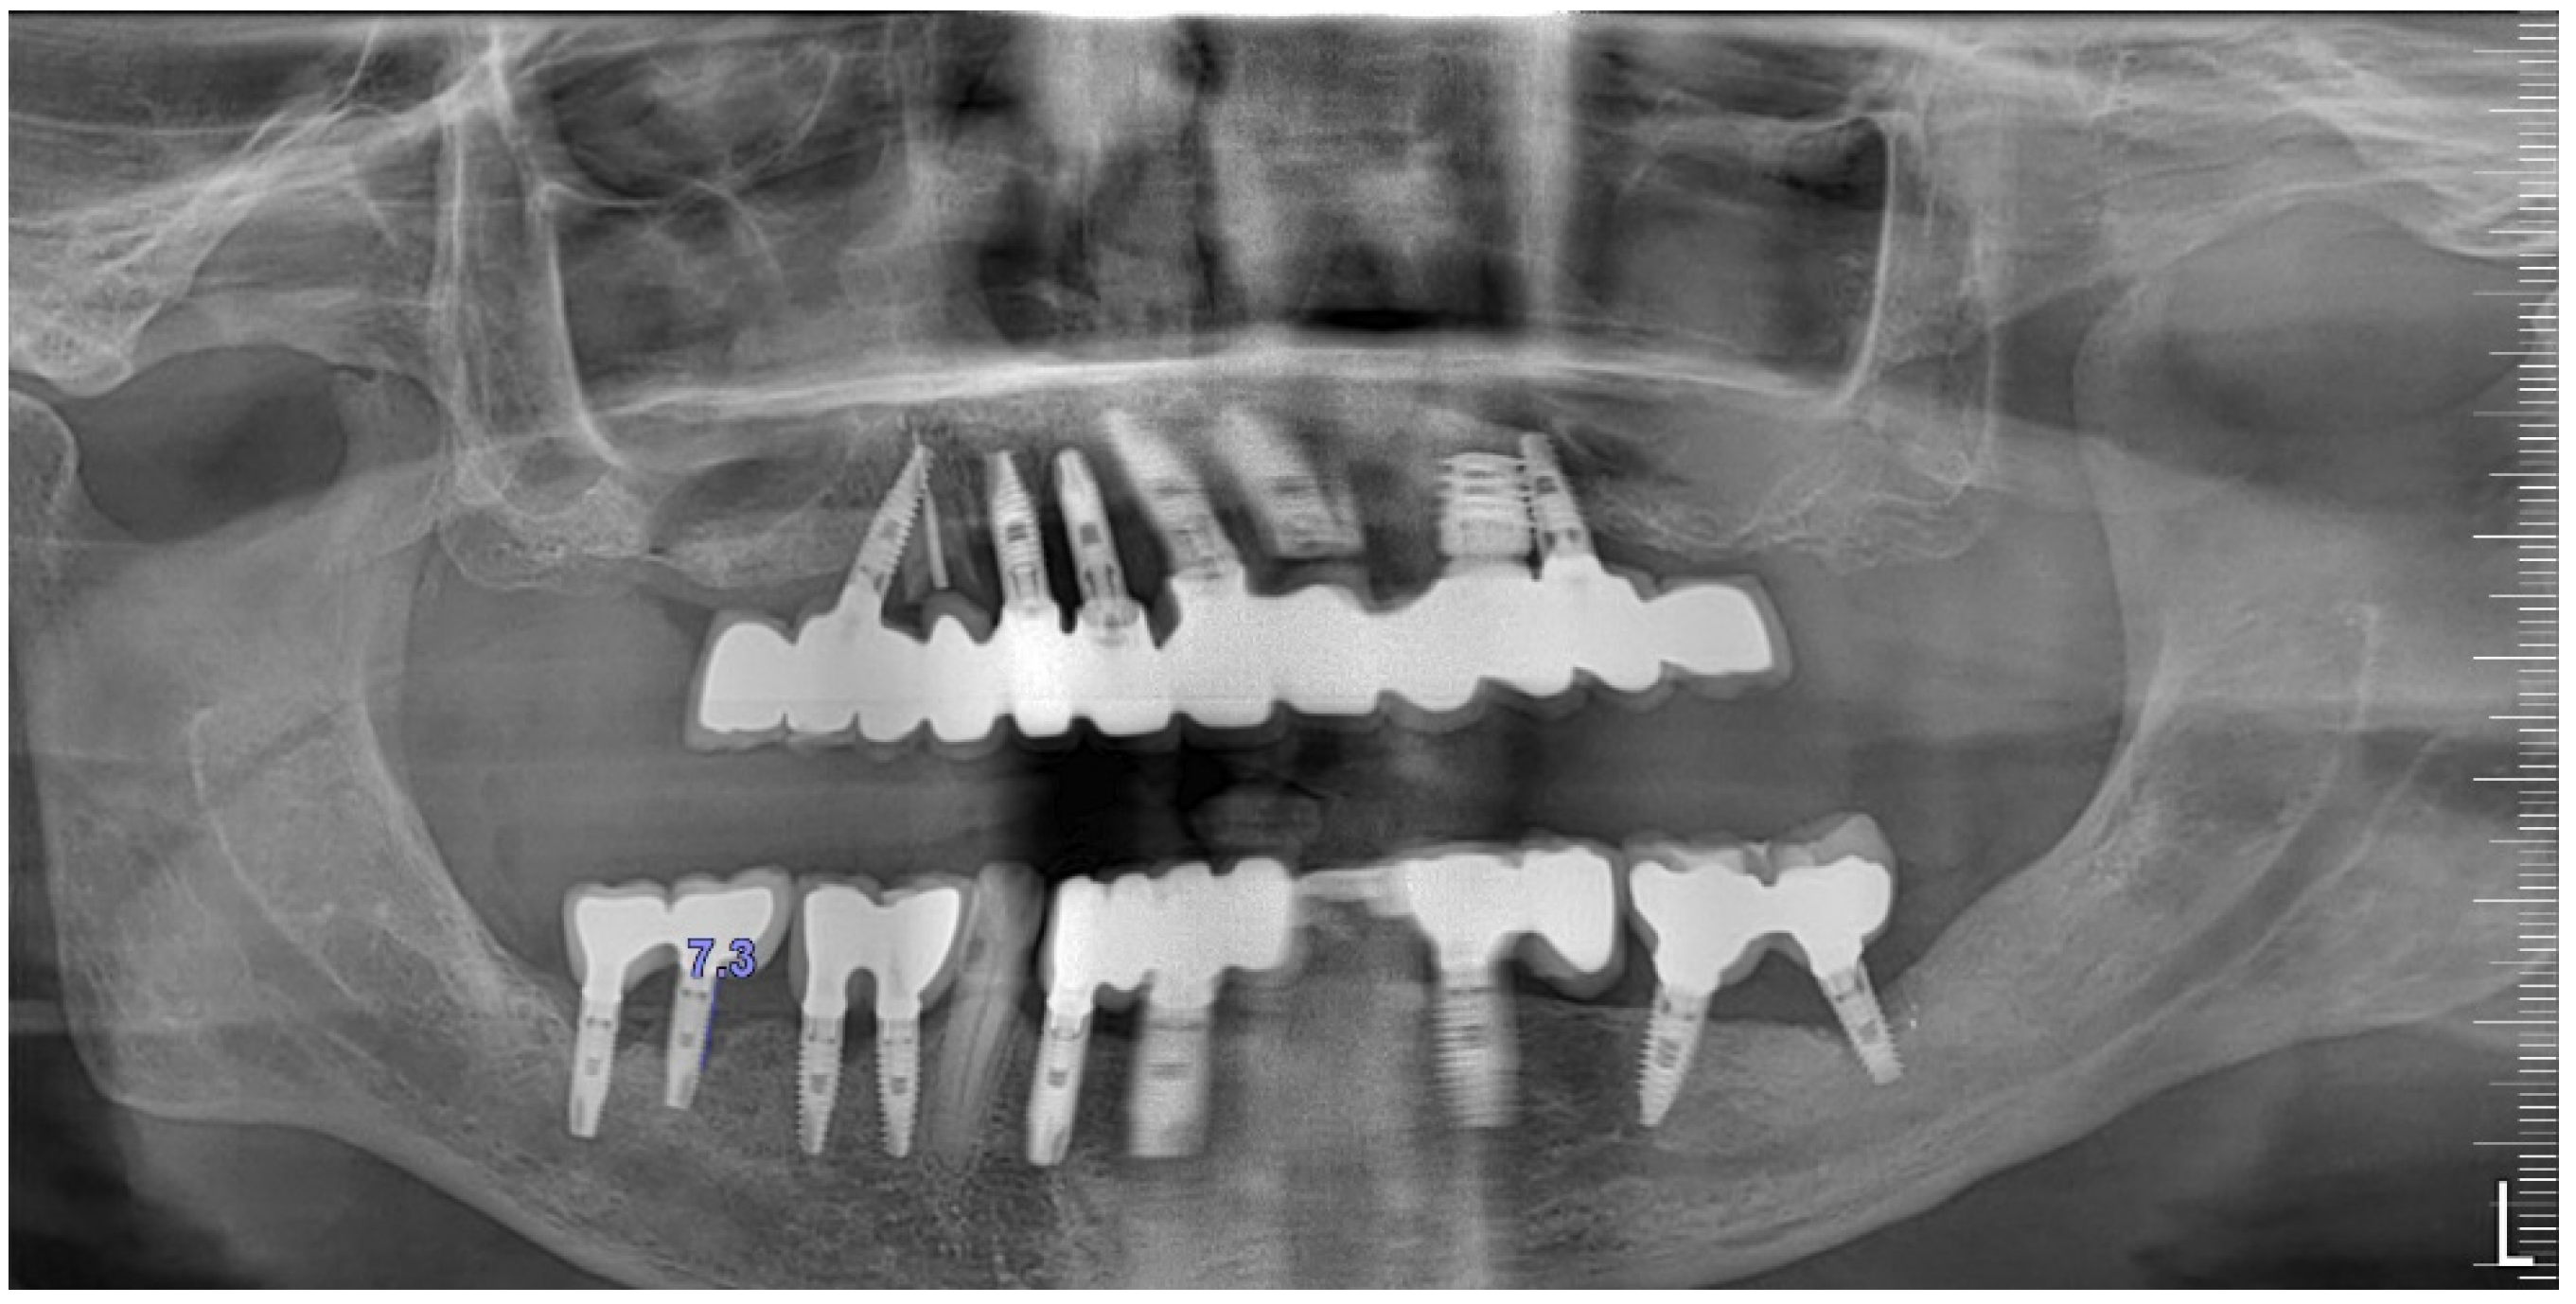

The intraoral examination revealed poor oral hygiene, characterized by significant plaque accumulation (over 65% plaque index) along the gingival margins and interdental areas. The periodontal status evidenced a progressive periodontal disease, with bleeding on probing (BoP) over 60%, mainly around all dental implants; peri-implant tissues possessed a high level of inflammatory condition, with localized swelling, high level of BoP, redness, and suppuration at the site of teeth #46 and #47, indicating local acute inflammation. The probing depth (PD) at site implant #46 exceeded 9 mm at both the mesial and distal sites, and at #47, the mesial site had a PD of 7.8mm, while the distal site showed lower bone loss (Figure 7).

Radiographically (Figure 8), the findings demonstrated full mouth edentulism, rehabilitated with upper and lower bridges and crowns supported by dental implants, as well as bone loss at #37, #46, and #47. The peri-apical radiograph (Figure 7) showed two dental implants, each measuring 13 mm, with bone loss around implant #46 (exceeding 60% of the implant length) and around implant #47 (exceeding 70% of the implant length).

The patient was provided with postoperative care instructions, including continuing with Moxypen 500 mg (Teva Pharmaceuticals, Petah Tikva, Israel) taken three times per day for three days, in addition to the medication previously prescribed. Follow-up appointments to monitor healing and treatment efficacy. The prosthesis adaptation to the gingiva was followed up for three months, when tissue healing was complete, and the need for readapting the prosthesis was evaluated. Considerations for readaptation included facilitating patient cleaning procedures. The patient was advised to enhance oral hygiene practices and scheduled for follow-up appointments. At the 14-month follow-up, the patient exhibited significant clinical improvements, with reduced PDs and evidence of bone regeneration around the affected implants (Figure 14). Notably, despite suboptimal oral hygiene practices being observed after 46 months, the patient maintained stable peri-implant conditions with minimal signs of mucositis, as evidenced by probing depths of 2 mm at implant #46 and 1 mm at implant #47, revealing significant improvements. This outcome underscores the potential durability of the surgical and regenerative interventions employed. However, it also highlights the critical importance of patient compliance with oral hygiene and regular maintenance visits in sustaining treatment outcomes, emphasizing the need for ongoing supportive peri-implant therapy. These findings suggest sustained peri-implant health over the long term. At the last follow-up, the patient reported being comfortable with the prosthesis and experiencing ease of cleaning. The intraoral X-rays indicated vertical bone gains of 7.5 mm around implant #46 and 8 mm around implant #47. Similar results were found after 43 months (Figure 14 and Figure 15), demonstrating the success of the treatment.

An 80-year-old male patient presented at the private dental office with severe mandibular pain, swelling, and mobility of a dental prosthesis retained by implants. The chief complaint was the lack of stability and mobility in mandible rehabilitation, with the symptoms already described. The medical history included controlled hypertension, hypercholesterolemia, anticoagulant therapy, and a history of heavy tobacco use, which ceased 15 years prior to the oral rehabilitation. The clinical examination revealed inadequate oral hygiene, extensive fixed-prosthesis and dental implant mobility, with PDs exceeding 10 mm; significant BoP was found, and severe vertical bone loss was radiographically confirmed around implant #33, #36, #37, #41, #43, #44, and #47 (Figure 16).

A generally healthy 63-year-old female presented to our clinic with chief complaints of foul odor and occasional pain emanating from dental implants located in the mandibular right quadrant (from implants #42 to #47). Clinical examination revealed peri-implantitis, with a high level of BoP and suppuration around the affected implants. The radiographic evaluation confirmed moderate-to-severe vertical bone loss, consistent with a diagnosis of peri-implantitis (Figure 19).

Figure 8. The initial panoramic radiograph reveals oral rehabilitation and bone loss in the lower posterior teeth.